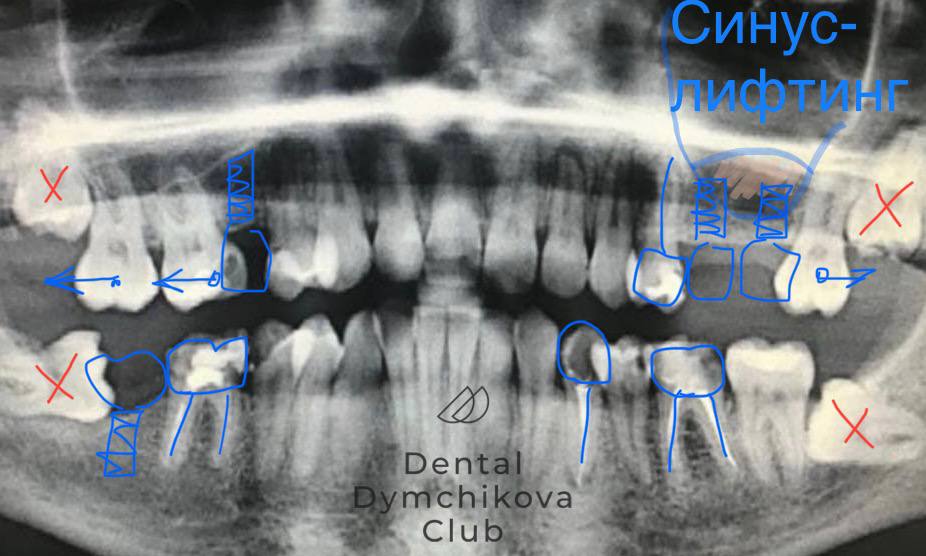

Ортодонтическое лечение, синус-лифтинг, имплантация, протезирование, лечение кариеса

Пациент, 33 года.

Жалобы: на неровные зубы, желание поменять мосты на задних зубах.

Исходные данные: скученность зубов, наличие кариесов, недостаток кости по высоте для установки имплантатов.

Лечение:

1) санация полости рта (лечение кариеса),

2) ортодонтическое лечение (брекеты, минивинты),

3) синус-лифтинг и имплантация в области отсутствующих зубов на этапе ортодонтического лечения,

4) протезирование зубов и имплантатов коронками.

Срок лечения: 2,4 года.

Доктора: Ефимова Дарья Юрьевна, Дымчикова Анна Вавиловна, Лебедева Адиса Тумэновна.